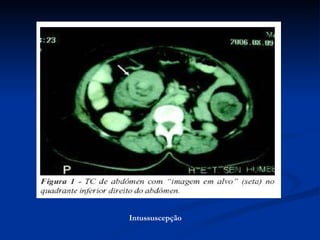

Diagnóstico Radiológico  Intussuscepção

Intussuscepção